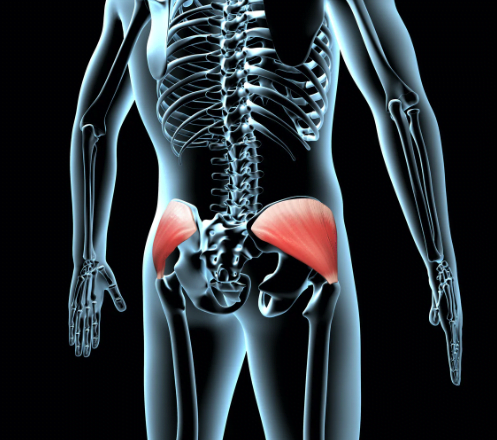

The new approach is a paradigm shift in the understanding of the assessment and treatment of lower back and extremities pain and dysfunction.

It’s significantly important for clinicians and patients.

The new approach is based on a new biomechanical discovery which will provide explanations to a multitude of considerations in the lower back and extremity pain as well as dysfunction.

If the new approach is applied correctly, it would enable clinicians to improve the patient’s chances of conservative treatment over surgical treatment, reduce or eliminate the for intraarticular injection and epidurals

- Review of current problems and challenges, and the need for new direction to address back and lower extremities pain and function.

- Explore Clinical Biomechanics: Introduction to a New Biomechanical Discovery, Reproduction of pain generating forces with example cases.

- Develop skills in the assessment of back and lower extremities pain and dysfunction.

- Develop a comprehensive and individualized treatment plan for patients with back and lower extremities pain and dysfunction.